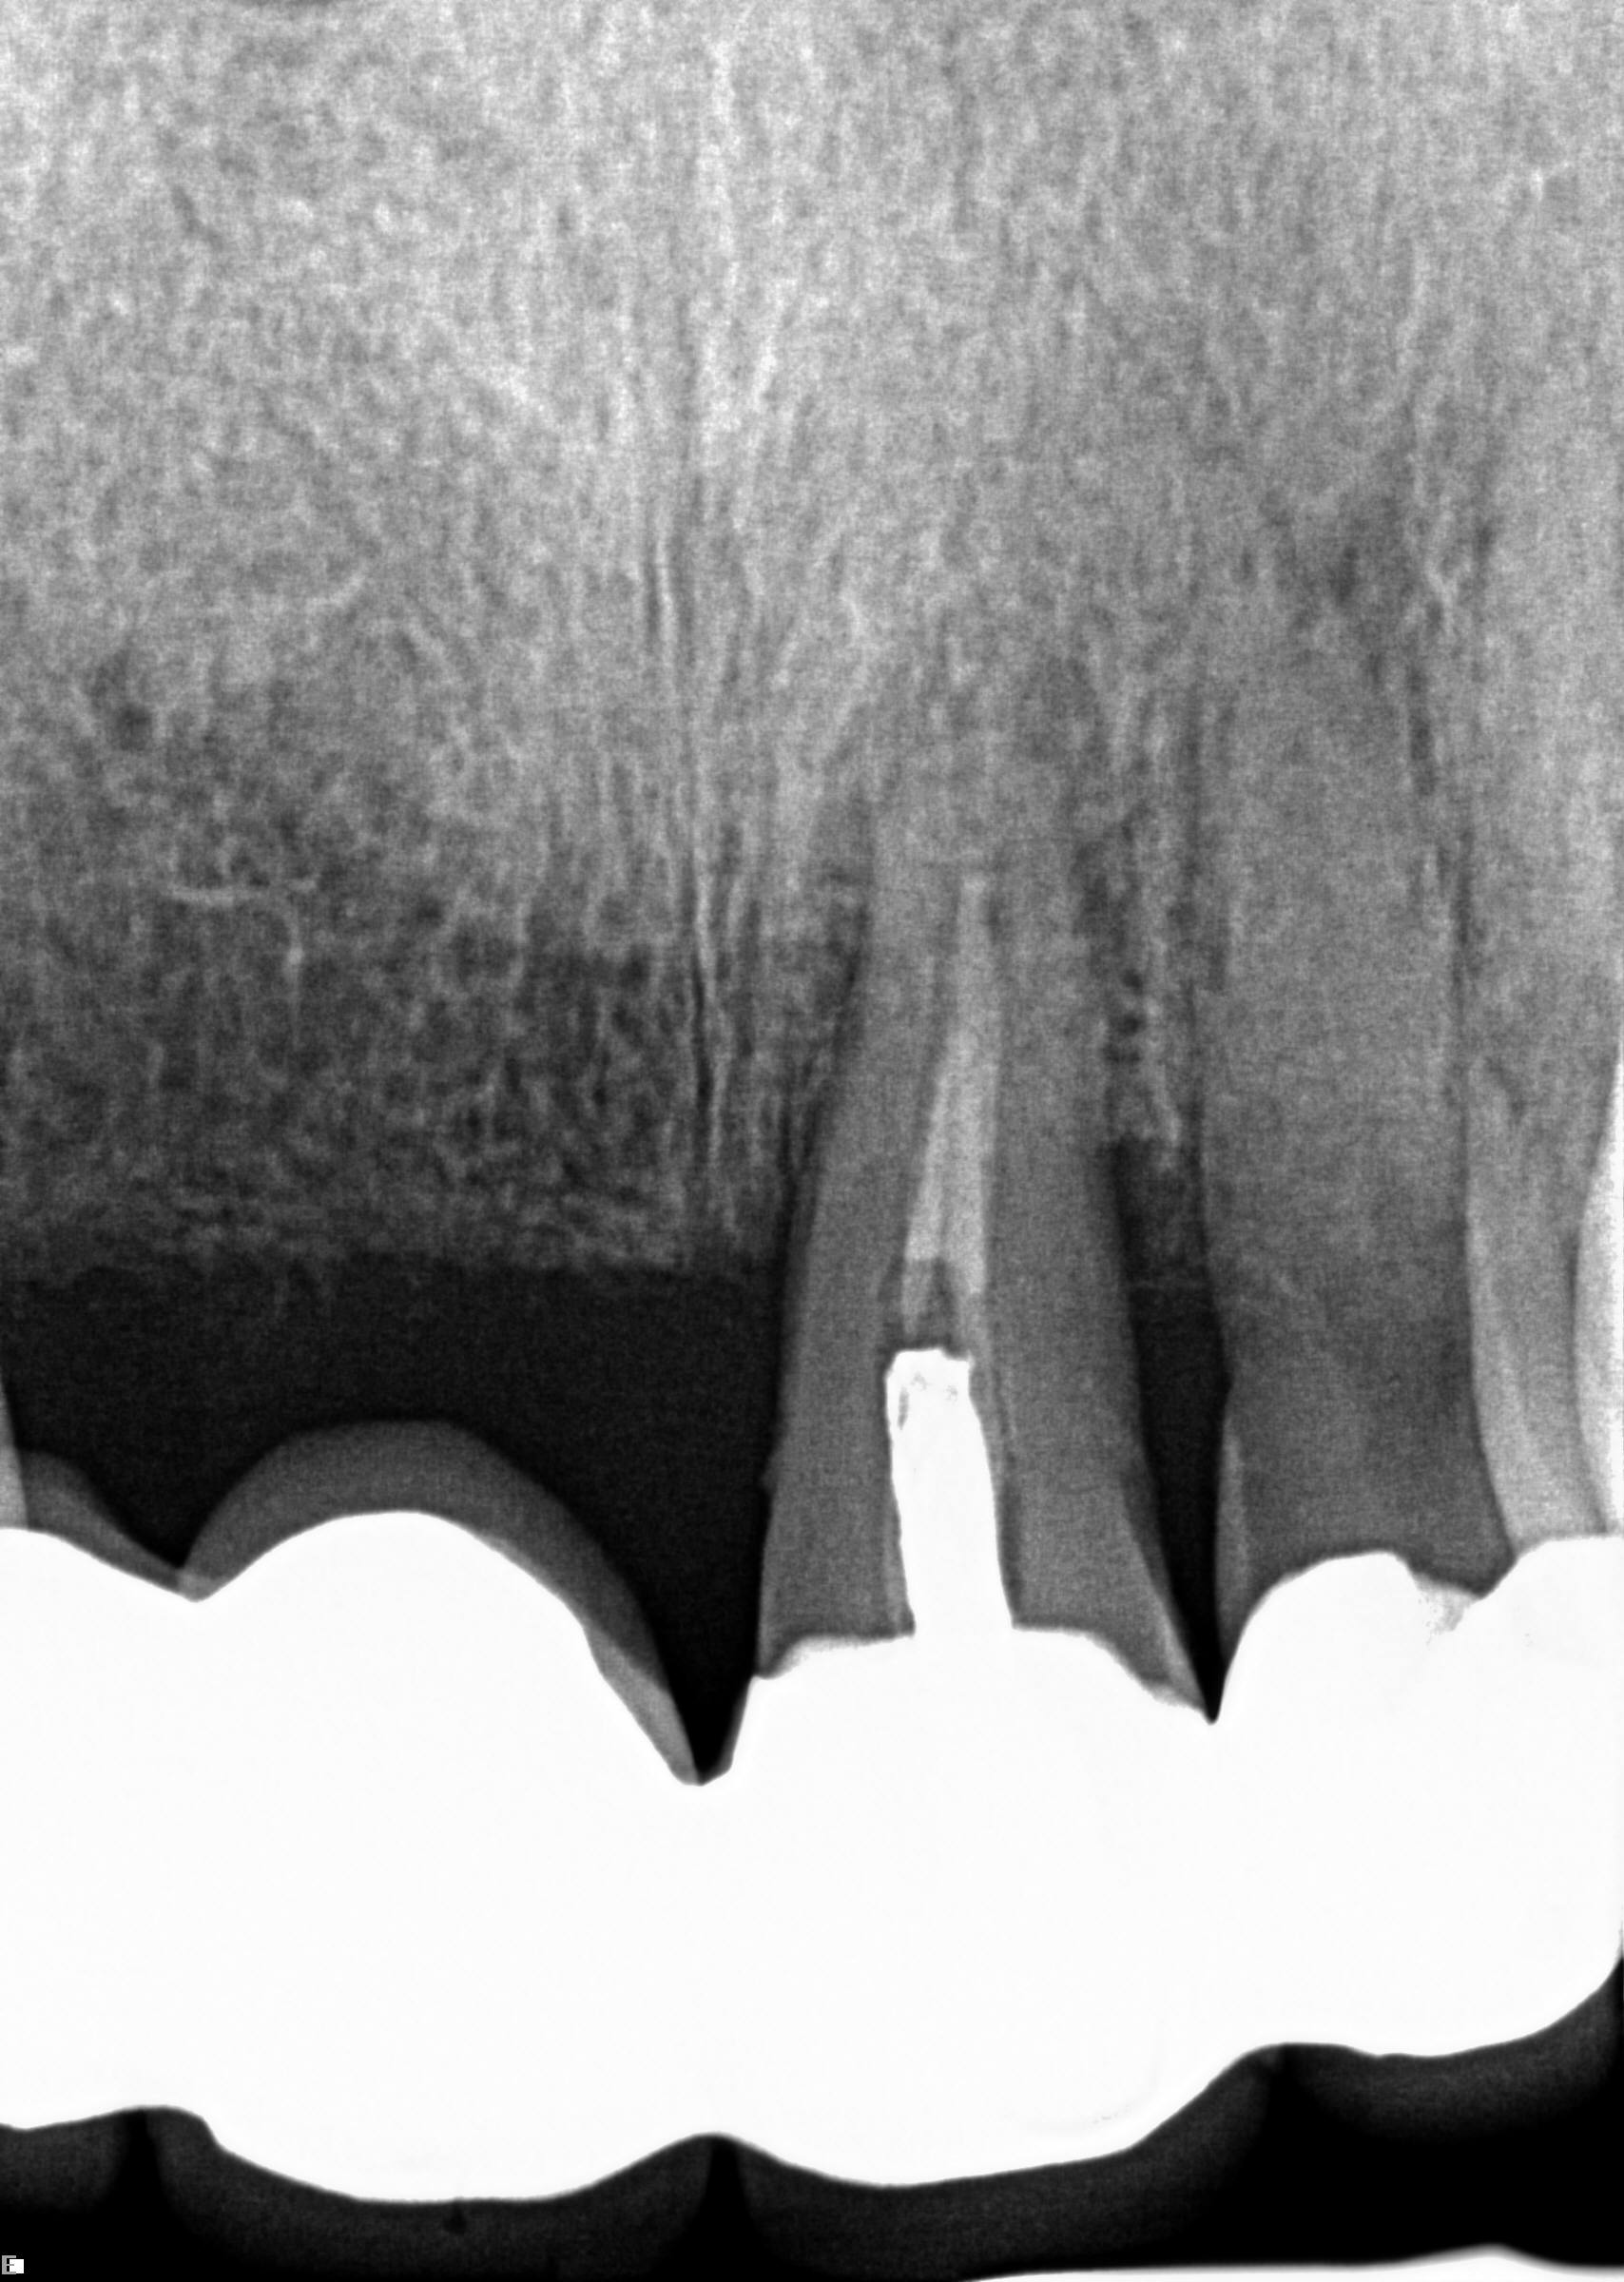

(17.) Case 3 initial radiograph of bridge on Nos. 6 through 9 and crown on No. 10.

Figure 17

(18.) Case 3 initial radiograph of bridge on Nos. 6 through 9 and crown on No. 10.

Figure 18

A 42-year-old man presented with a very loose bridge on Nos. 6 through 9 with periodontally compromised retainers on Nos. 6 and 9 (Figure 17 through Figure 19), and endodontically involved No. 10 with a calcified canal. Teeth Nos. 6, 9, and 10 were extracted, the sockets fully debrided, and pontic soft tissue on Nos. 7 and 8 sculpted to be symmetrical in soft tissue contour with the contralateral lateral incisor and central incisor locations. Implants were secured in position Nos. 6 through 10 (Figure 20) in excess of 45 Ncm, the bone was milled to provide unimpeded seating of temporary abutments, and temporary crowns were fabricated chairside and adjusted to be out of occlusion in centric relation and all excursions. The temporary crowns were cemented after extrusion of excess cement extraorally and the patient was prescribed antibiotics, analgesics, and instructed in postoperative care particular to immediately provisionally restored implants. At 6 months, integration was confirmed (Figure 20 through Figure 23) and after placement of scanning abutments, the implants and soft tissues were scanned. Final crowns were fabricated from the scanned images and were cemented after extrusion of excess cement extraorally (Figure 24 through Figure 26), and oral hygiene procedures were reviewed.